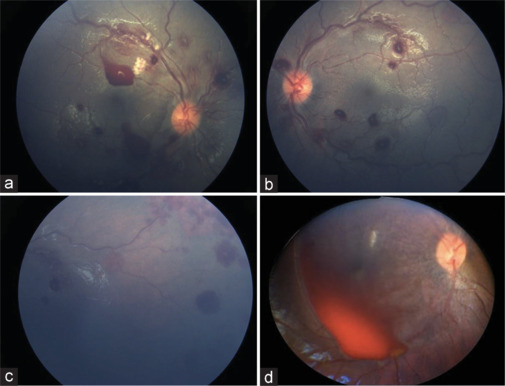

Results: A total of 25 (50 eyes) cases of AHT had an eye examination documented in the electronic patients' records. The majority were males 19 (76%), and <6 months of age 10 (40%). About half of the children were healthy 13 (52%), and 12 (48%) had underlying physical illness. All patients had computed tomography scans. Subdural bleeding was noted in 22 (88%), 1 (4%) had epidural, and 4 (16%) had subarachnoid bleed. External ocular signs were noted in 8 (32%) patients only, including raccoon eyes, periorbital bruises, subconjunctival hemorrhage, and nonfixating eyes. Fundus findings were bilateral in 18 (72%), unilateral in 2 (8%), and normal in 5 (20%). In those with findings, the majority of 34 (68%) eyes had multiple retinal hemorrhages, 4 (8%) had vitreous hemorrhages, 2 (4%) retinal detachments, and 1 (2%) retinoschisis.

Conclusion: Fundus examination is an important part of the comprehensive examination of children with suspected AHT; the majority of patients had an abnormal fundus examination with the tendency of bilateral findings.